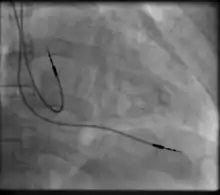

Transvenous pacing, when used for temporary pacing, is an alternative to transcutaneous pacing. A pacemaker wire is placed into a vein, under sterile conditions, and then passed into either the right atrium or right ventricle. The pacing wire is then connected to an external pacemaker outside the body. Transvenous pacing is often used as a bridge to permanent pacemaker placement. It can be kept in place until a permanent pacemaker is implanted or until there is no longer a need for a pacemaker and then it is removed.

Permanent pacing with an implantable pacemaker involves transvenous placement of one or more pacing electrodes within a chamber, or chambers, of the heart, while the pacemaker is implanted inside the skin under the clavicle. The procedure is performed by incision of a suitable vein into which the electrode lead is inserted and passed along the vein, through the valve of the heart, until positioned in the chamber. The procedure is facilitated by fluoroscopy which enables the physician to view the passage of the electrode lead. After satisfactory lodgement of the electrode is confirmed, the opposite end of the electrode lead is connected to the pacemaker generator.